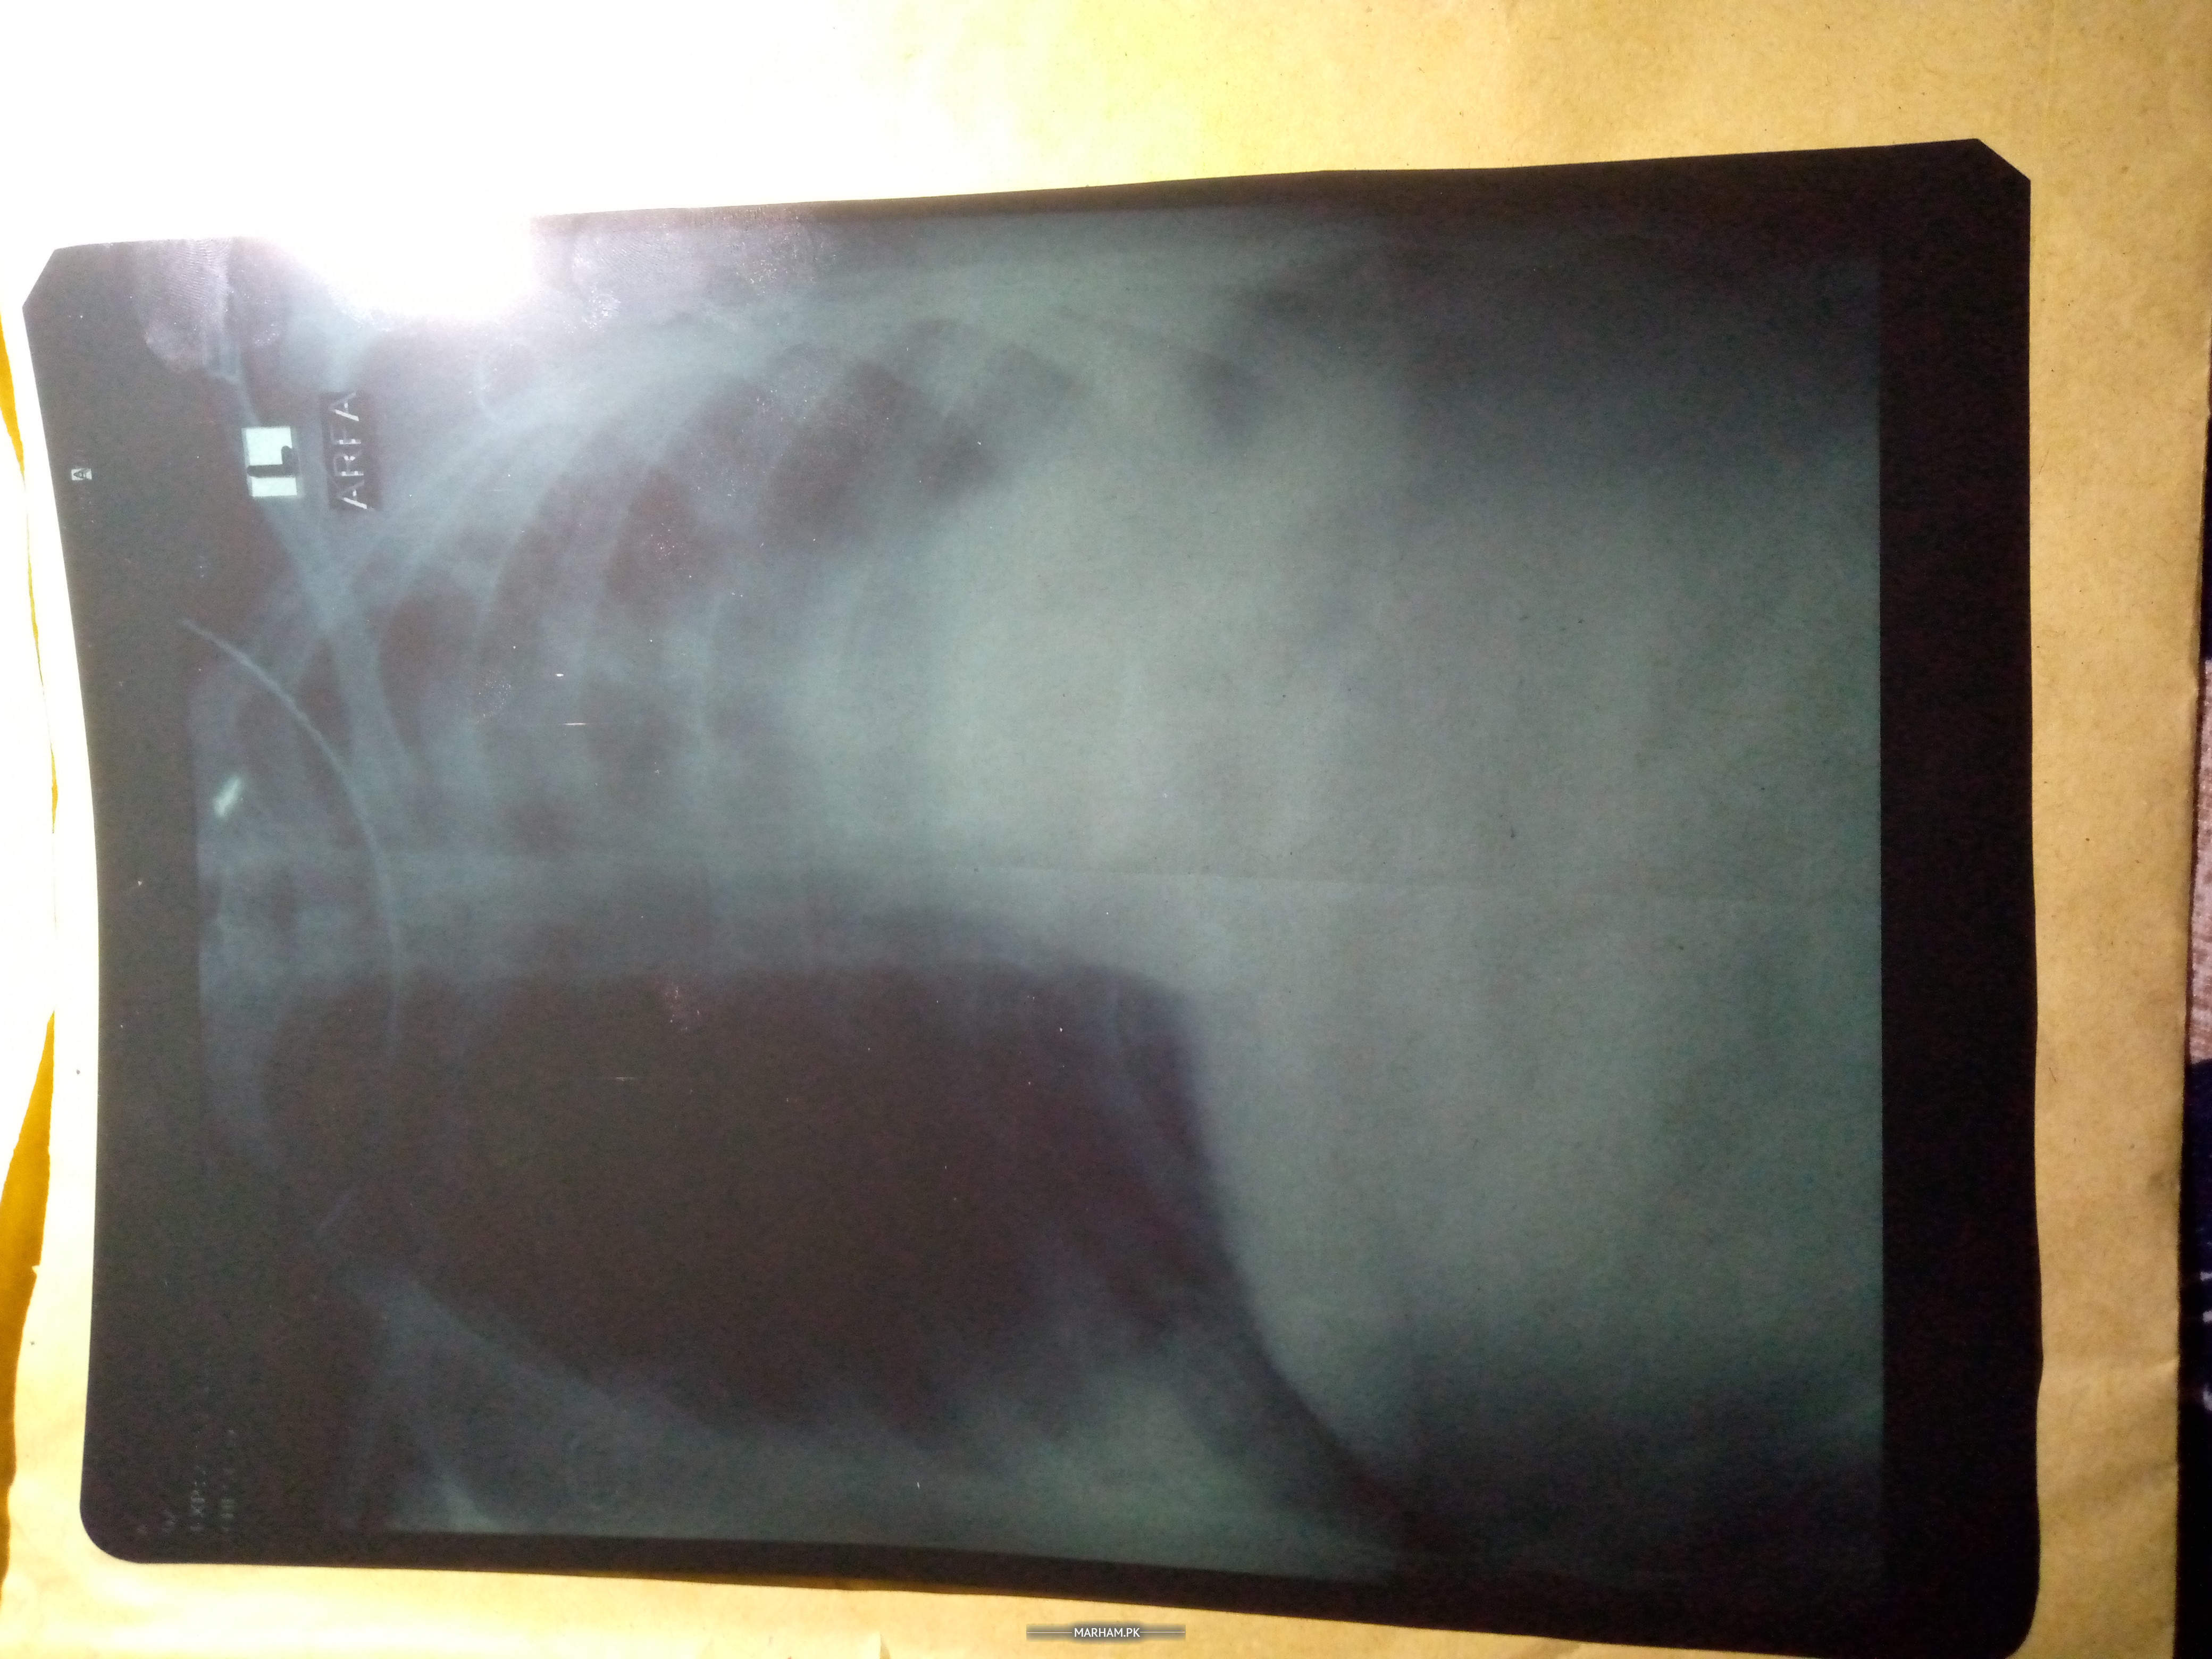

Mera ek lung demage hai ab us k sat hat or per Mai dard or sojan hai doc k pas gae to doc ny kaha k per Mai Pani hai ye kia waja hoskti hai ?

x-ray